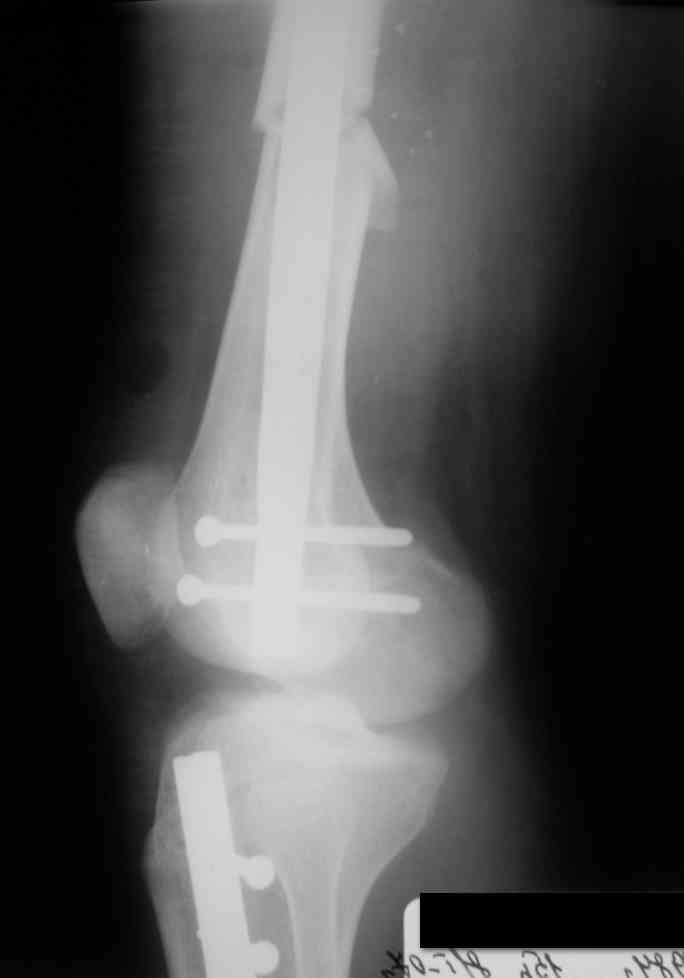

Дорогой Александр. Имею скромный опыт использования системы Fixion при переломах плеча, бедра и тибии. Всего 18 наблюдений с сентября 2006 г. Результаты отличные. Гвоздь индивидуален для каждого медуллярного канала. Легко имплантируется как в узкий, так и в деформированный канал. Это позволяет применять метод интрамедулярного остеосинтеза без ненужных потерь времени операции, флюороскопии и реально снижает крвопотерю и операционный риск. Удаление происходит без проблем. Особенно интересны больные с ипсилатеральными переломами бедра и голени.

Да, спасибо за интересные иллюстрации. Получилось очень симпатично. На большеберцовой кости непременно надо было винты? Там же был торцовый упор, перелом в средней трети?

Сам гвоздь является универсальным по отношению к любому костно-мозговому каналу. Этим объясняется его возможность принимать форму канала в зависимости от индивидуальных особенностей формы кости. Перед введением гвоздь в сжатом состоянии позволяет его установить без особых усилий, что значительно экономит время (и нервы) хирурга. Учитывая, что гвоздь имеет возможность расширяться до 60% своего первоначального диаметра, а диаметр сдутого штифта выбирается несколько меньше толщины канала кости, легко достигается репозиция костных отломков закрытым путем (если перелом не оскольчатый). Имеется небольшой опыт установки при многооскольчатом характере перелома 7 гвоздей. В 4 случаях приходилось открывать место перелома, из них в 3 случаях приходилось накладывать серкляж.

Во всех остальных случаях линию перелома открывали либо при 3-4 недельной давности перелома, либо при интерпозиции мягких тканей. Блокированные гвозди очень хорошо устанавливать при переломе находящемся в непосредственной близости от сустава.